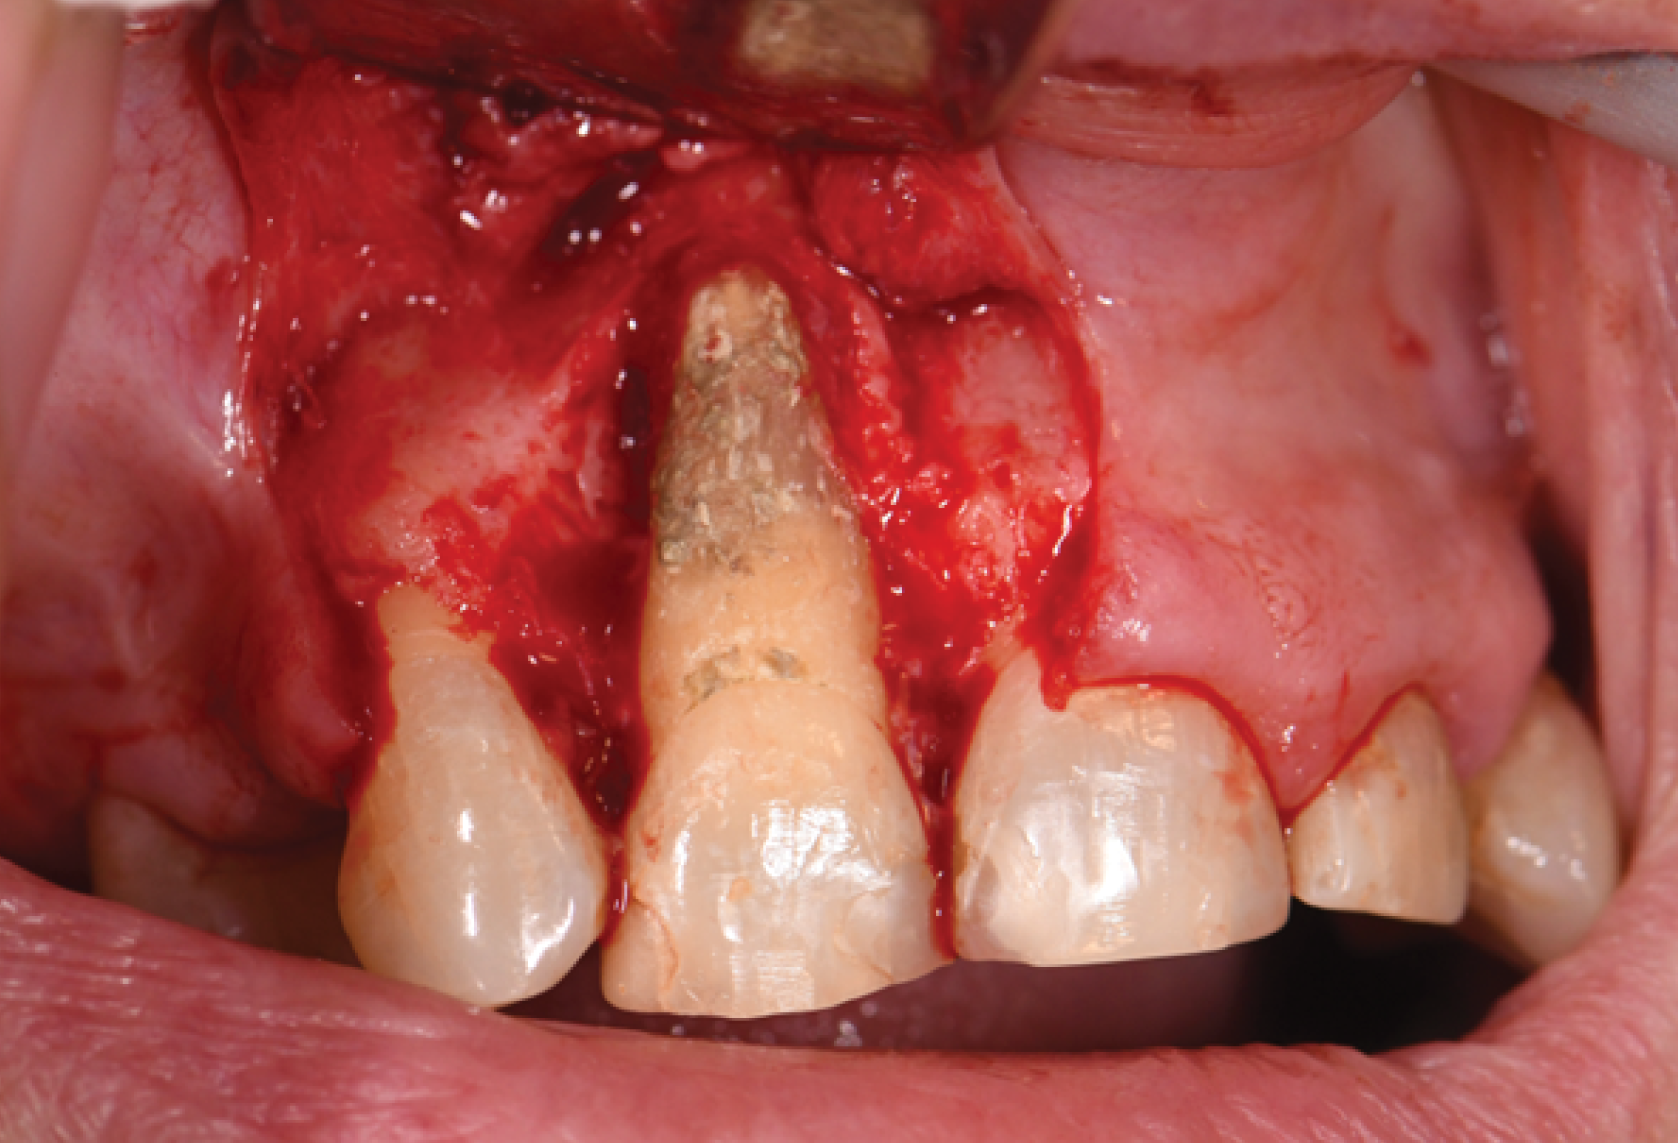

The periodontal dilemma:

When to save, when to let go?

When to save, when to let go?

Course Topic

Periodontics

● Understanding the literature of prognosticating periodontally compromised dentition

● What are some of the factors periodontists assess to diagnose the prognosis of the tooth?

● Additional considerations before deciding whether save or remove teeth